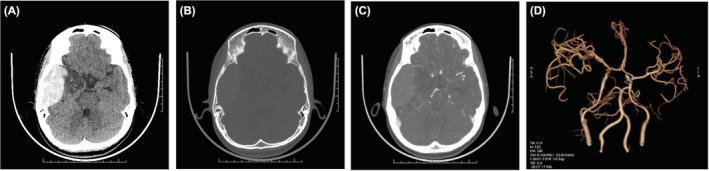

Spontaneous extradural hematoma in Sickle cell disease is rare neurological complication with few cases reported in the English literature. We report a case of a 16-year-old male patient who was previously diagnosed with Sickle Cell Beta Thalassemia and presented with severe headache and vomiting for 3 days. An emergency CT scan of the head demonstrated right-sided acute parietal extradural hematoma with mass effect. Patient underwent emergent craniotomy with evacuation of the hematoma. Patient recovered completely. Although calvarial infarction has been associated with extradural hematoma, an absence of it makes our case distinct. A high index of suspicion should be made in SCD patients for possibility of EDH in progressive headache.

镰状细胞病中的自发性硬膜外血肿是一种罕见的神经并发症,英文文献中报道的病例很少。我们报告一例16岁男性患者,该患者先前被诊断为镰状细胞β地中海贫血,出现严重头痛和呕吐3天。头部急诊CT扫描显示右侧急性顶叶硬膜外血肿并伴有占位效应。患者接受了紧急开颅血肿清除术。患者完全康复。虽然颅骨梗死与硬膜外血肿有关,但我们的病例没有颅骨梗死,这使其具有独特性。对于患有进行性头痛的镰状细胞病患者,应高度怀疑其有发生硬膜外血肿的可能性。